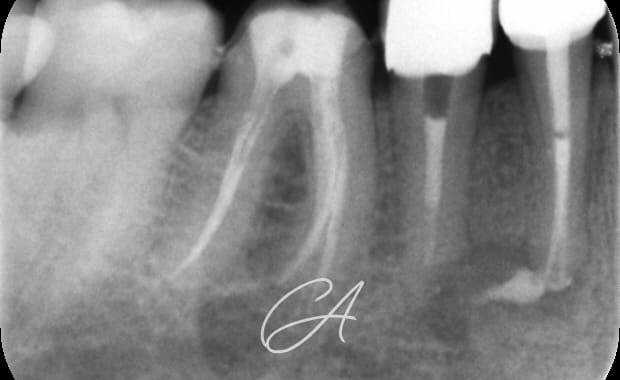

Buongiorno a tutti, oggi mi piacerebbe condividere con voi un caso multidisciplinare. Il paziente si presenta per ricorrenti ascessi in sede 45 e 44. Entrambi gli elementi vengono sagomati con strumenti espansivi. L'elemento 44 viene otturato con tecnica single cone e bioceramico mentre l'elemento 45, a causa del diametro importante (> 80) e per la forma ovale del sistema endodontico, viene sottoposto ad apical plug in MTA. Gli elementi vengono poi sottoposti a fase ricostruttiva (in seguito a disassembling delle corone) e limati con tecnica BOPT e il provvisorio viene mantenuto diversi mesi per condizionare i tessuti. Tutto bene, fino a quando non mi sono fatto realizzare le corone definitive. Ho notato subito che avrei ottenuto una vistosa disomogeneità dei livelli gengivali; ho pertanto deciso di proporre al paziente (a mie spese), un innesto gengivale libero per l'ispessimento dei tessuti gengivali. Ho quindi modificato la lunghezza e il profilo di emergenza della corona 44 e cementate entrambre le corone con cemento provvisorio in attesa della maturazione dei tessuti.

Il controllo dei tessuti gengivali è ancora precoce ma la guarigione radiografica periapicale è a 1 anno (ultima radiografia visibile).